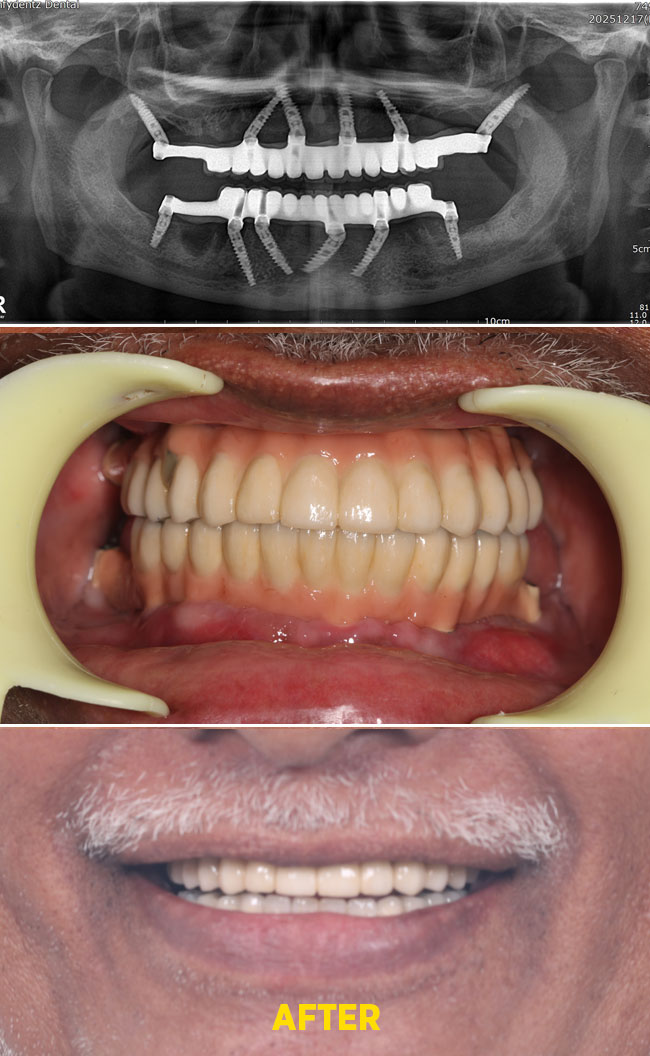

Case - 3